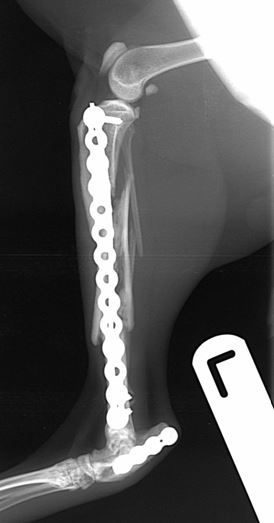

radiographic union of both fractures        radiographic union of both fractures

Fig. 4. At 10-weeks there is radiographic union of both fractures

The cat was weight bearing the day after surgery and has gone on to have an uneventful recovery